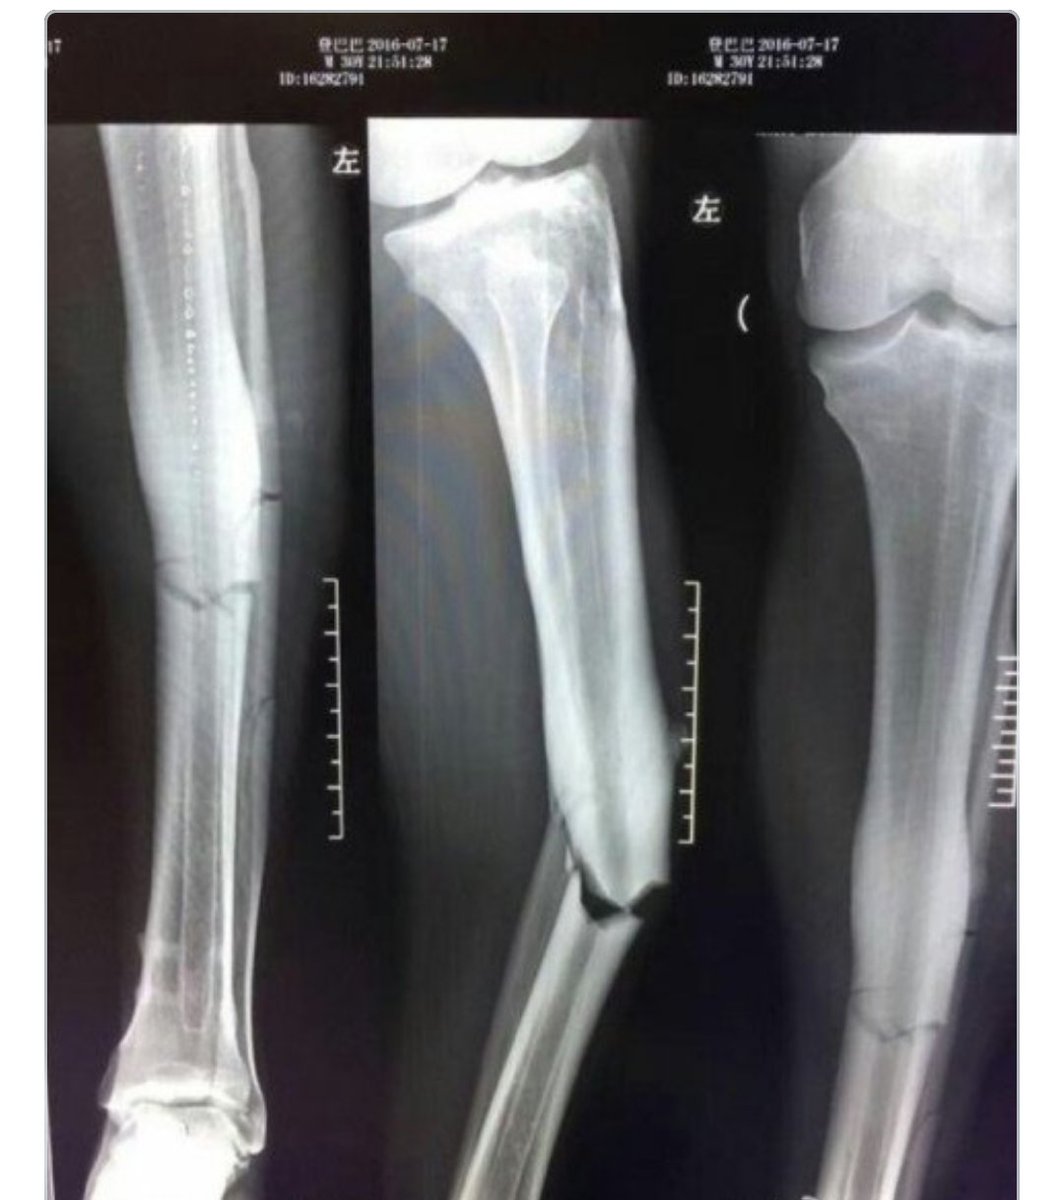

Title : Horor Inilah Hasil X Ray Patahan Kaki Demba Ba Bola Net Source : www.bola.net Open New Window

Title : Inilah Hasil X Ray Cedera Horor Demba Ba Goal Com Source : www.goal.com Open New Window

Title : Foto Mengerikan Ini Hasil X Ray Dari Patah Tulang Demba Ba Indosport Source : www.indosport.com Open New Window